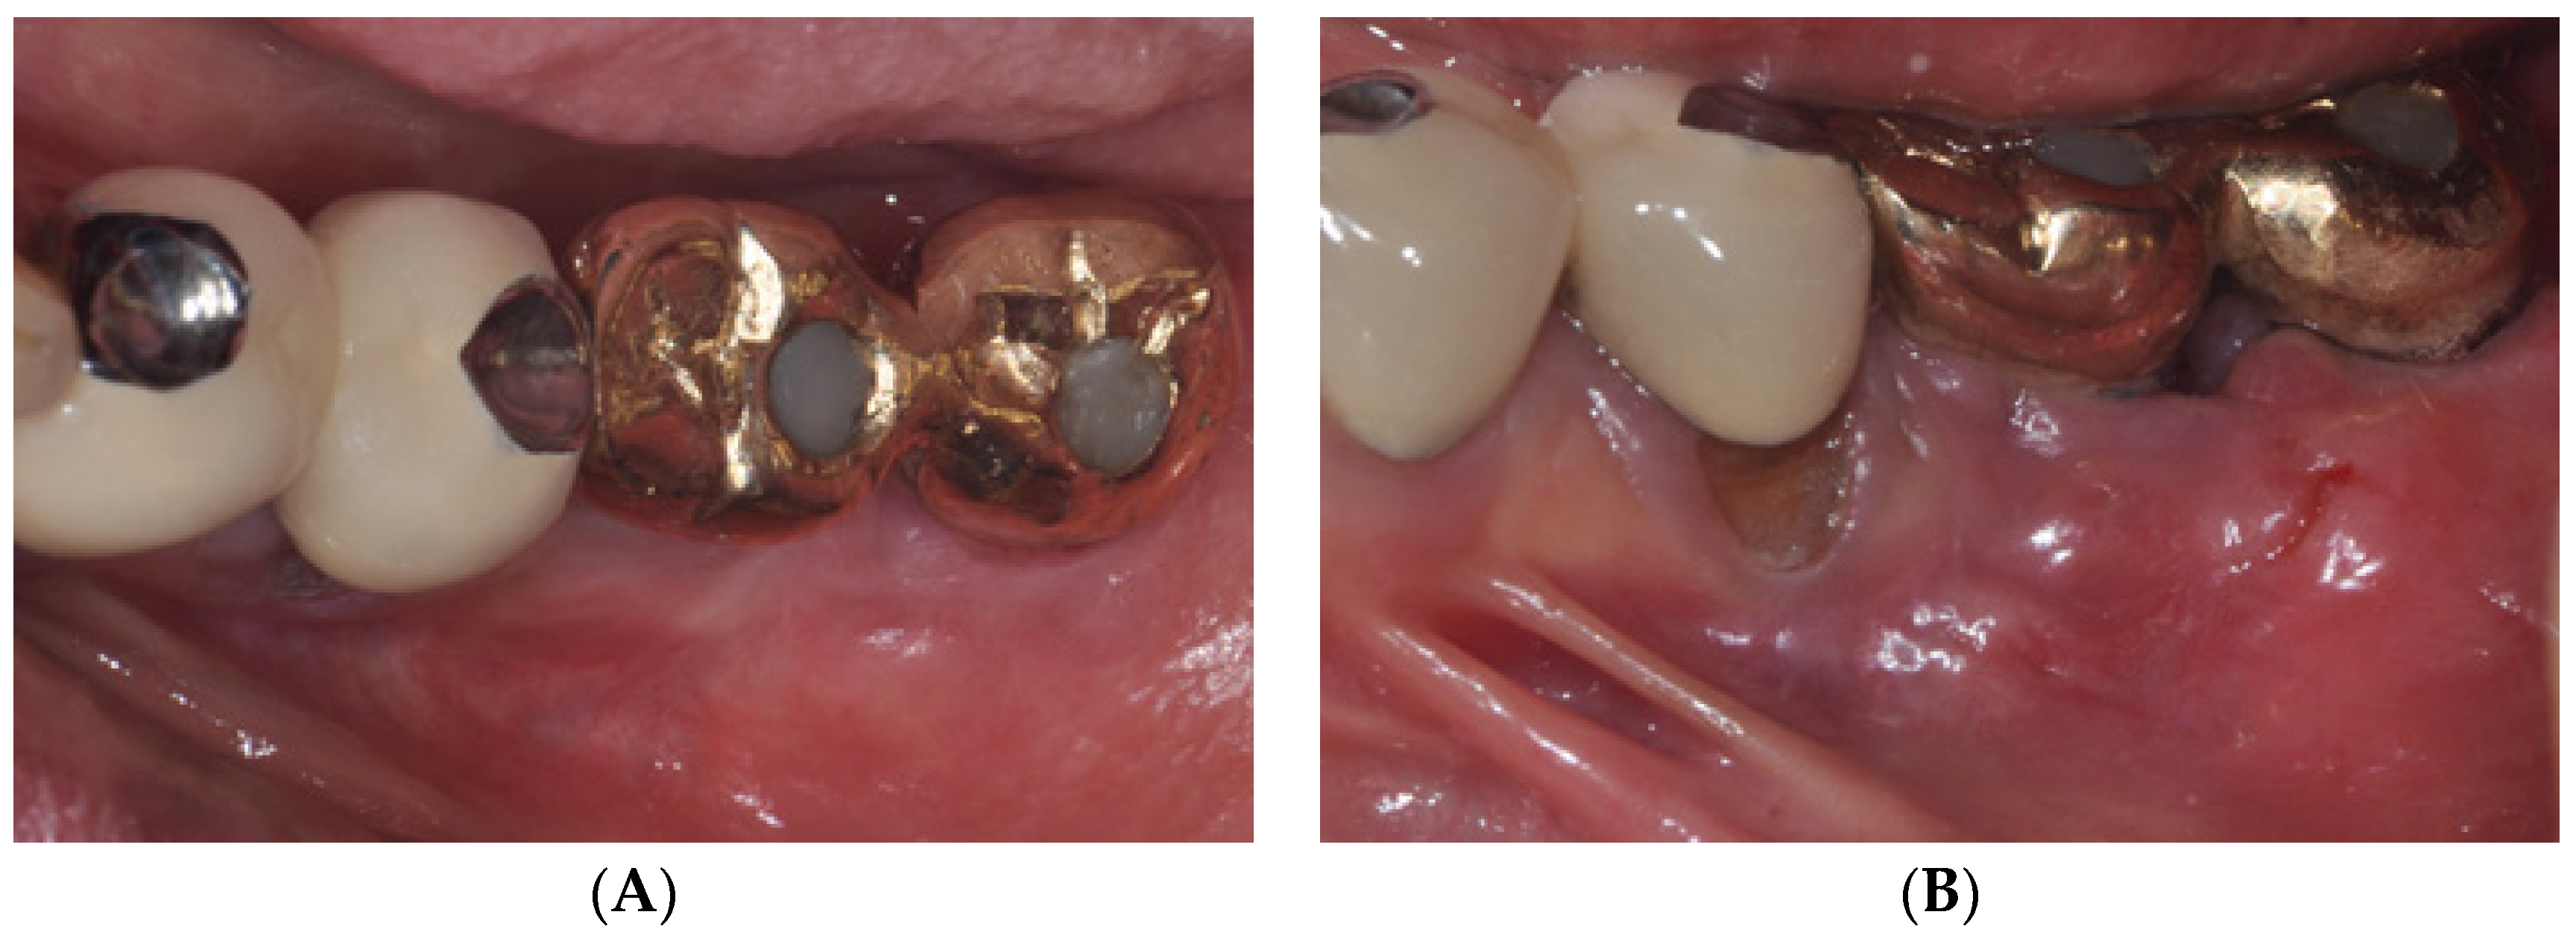

2.1. Surgical Procedures of Er:YAG Laser-Assisted Periosteal Fenestration (LA-PF)

2.2. Case